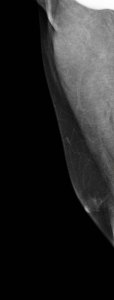

Se le realiza ampliación de estudio de mamografía, ambas mediolaterales. Imágenes 10 y 11:

Observamos claramente contorno nodular de la mama izquierda.